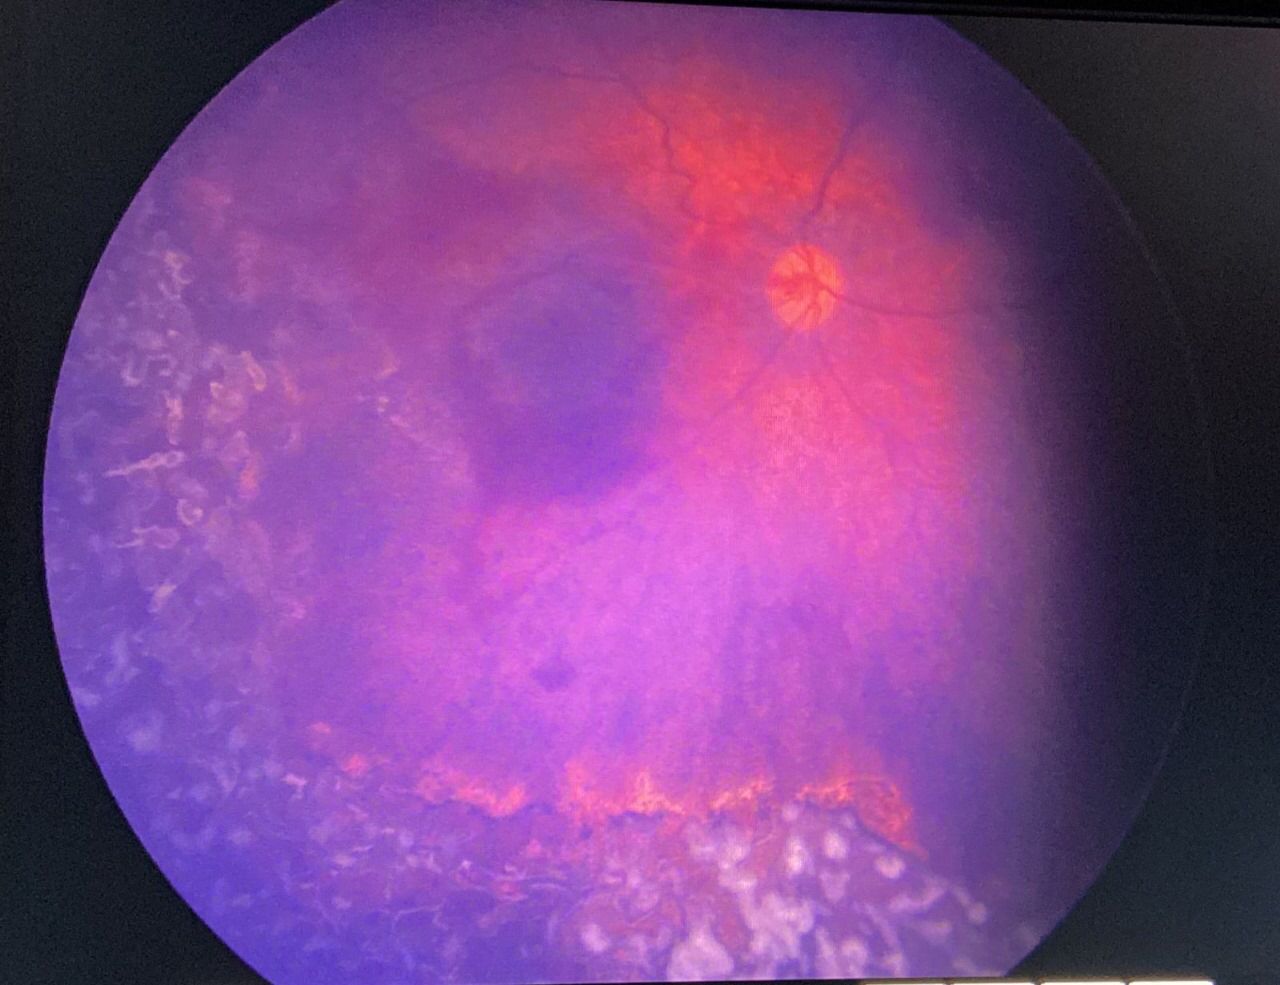

نجح مستشفى حراء العام عضو تجمع مكة المكرمة الصحي في إجراء عملية عاجلة بالشبكية لطفلة تبلغ من العمر 3 أشهر مصابة بمرض السلس الصباغي وهي متلازمة نادرة تحدث بنسبة 0.0025% لدى بعض الناس وتؤثر على الجلد والأسنان والجهاز العصبي بالإضافة لشبكية العين

وبين التجمع الصحي أن الشبكية كانت متضررة في كلتا العينين وبالأخص العين اليمنى وأجريت عملية الليزر للعينين تحت التخدير العام بأسرع وقت ممكن وذلك بعد فحص المريضة من قبل فريق التخدير بقيادة استشاري التخدير الدكتور شادي بركات وتكللت العملية بالنجاح وخرجت الطفلة وهي بأتم الصحة